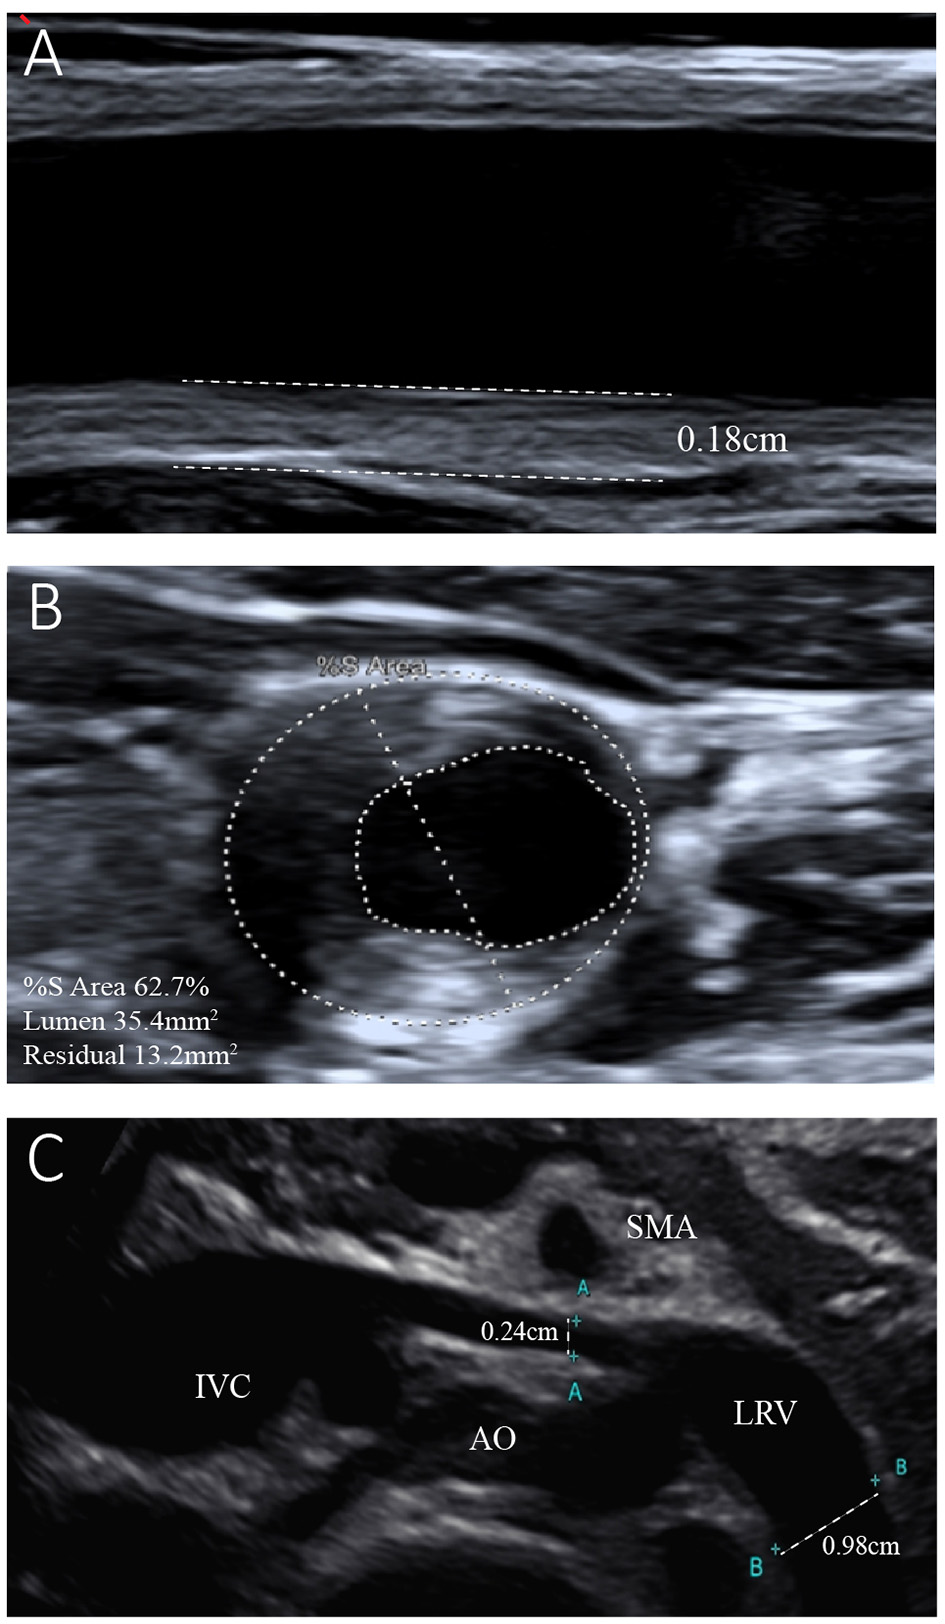

Figure 2

Ultrasonogram of the left common carotid artery and left renal vein. (A) Reveals left carotid atherosclerosis with plaque formation and intima-media thickness of the left common carotid artery of 0.18 cm. (B) Shows 62.7% stenosis of the left common carotid artery. (C) Shows entrapment of the left renal vein (LRV) between the aorta (AO) and superior mesenteric artery (SMA). The internal diameter of the LRV was 0.24 cm, while that of the distal segment was 0.98 cm.

The results of the girl's laboratory tests were as follows (partly shown in Table 1): total cholesterol 14.65 mmol/L; LDL-C 12.92 mmol/L; high-density lipoprotein cholesterol (HDL-C), 0.93 mmol/L; triglyceride 1.68 mmol/L; apolipoprotein B 3.85 g/L; apolipoprotein A1 1.14 g/L; lipoprotein(a) 602.2 mg/L; creatinine 19 μmol/L; estimated glomerular filtration rate 193.83 ml/min/1.73 m2; urea nitrogen 2.1 mmol/L; and albumin, 29 g/L. A dipstick urinalysis showed hematuria (2+) and proteinuria (2+); urine sediment showed a few red cells, 60% of which were normal; and urinary protein was 7.25 g/24 h. No malignancies or thyroid disease was discovered, and other routine blood examinations, such as anti-PLA2R, antinuclear, anti-double-stranded DNA, anti-Smith, anti-RNP, and anti-neutrophil cytoplasmic antibodies, were all negative. Complements C3 and C4, immunoglobulin, rheumatoid factor, and anti-streptolysin levels were within normal range. She was seronegative for human immunodeficiency virus and hepatitis B and C viruses. Electrocardiography and echocardiography indicated normal cardiac structure and function. Ultrasonography of the arteries showed atherosclerotic plaques in the bilateral carotid arteries (Figures 2A,B), subclavian artery, innominate artery bifurcation, and abdominal aorta. Ultrasound of the urinary system showed no abnormalities, while that of the renal veins showed entrapment of the left renal vein between the aorta and superior mesenteric artery, consistent with nutcracker syndrome (Figure 2C). To further elucidate the cause of the high urinary protein level, a renal biopsy was performed. Immunofluorescence microscopy revealed diffuse granular deposition of IgG++, C3++, IgG1 +-++, IgG2 ++, IgG3 +, and PLA2R + + ++ in vascular areas. GBM was diffusely thickened, and spike formation was observed on the epithelial side. Granules and balloon-cell degeneration were visible in the renal tubular epithelial cells. No obvious abnormalities were observed in the interstitium or small blood vessels. In addition, no lipid deposition was observed, and no significant staining of Oil Red O was noted (Figure 3). The pathology of renal biopsy demonstrated MN (stage II), but atypical membranous nephropathy might not be excluded, with electron-dense deposition in the subepithelial area, basement membrane, and mesangial zone.